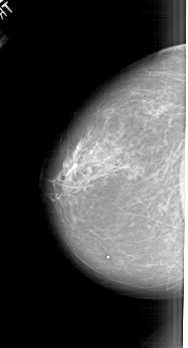

A_1620_1.RIGHT_MLO

RIGHT_MLO LINES 6481 PIXELS_PER_LINE 3466 BITS_PER_PIXEL 12 RESOLUTION 43.5 OVERLAY